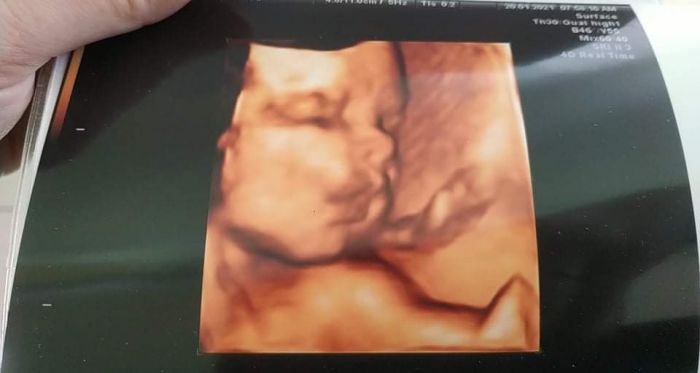

Holky tak my dnesky byli na ultrazvuku, tak máme cca 1500g, což je v normě k tomuto týdnu :) krásně šlo vidět, jak si malýz zívnul, bylo to úplně úžasné :) jen teda nejsme ještě otočení. Jinak sem už taky začala nakupovat plenky a hygienické potřeby do porodnice a včera sem začala třídit miminkovske věci, tak budu behem 14dni už taky prát :). No u nás v noci pršelo a ráno to totálně namrzlo w klouzalo to když jsme jeli k doktorom, naštěstí sme v pořádku dojeli :)